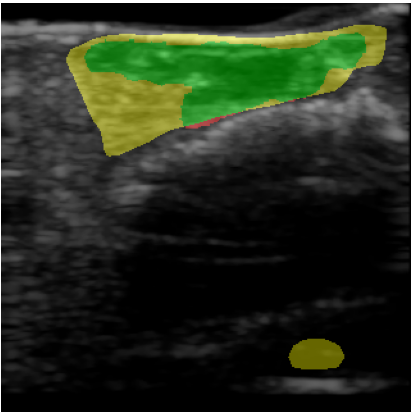

Chronic wounds including diabetic and arterial/venous insufficiency injuries have become a major burden for healthcare systems worldwide. Demographic changes suggest that wound care will play an even bigger role in the coming decades. Predicting and monitoring response to therapy in wound care is currently largely based on visual inspection with little information on the underlying tissue. Thus, there is an urgent unmet need for innovative approaches that facilitate personalized diagnostics and treatments at the point-of-care. It has been recently shown that ultrasound imaging can monitor response to therapy in wound care, but this work required onerous manual image annotations. In this study, we present initial results of a deep learning-based automatic segmentation of cross-sectional wound size in ultrasound images and identify requirements and challenges for future research on this application. Evaluation of the segmentation results underscores the potential of the proposed deep learning approach to complement non-invasive imaging with Dice scores of 0.34 (U-Net, FCN) and 0.27 (ResNet-U-Net) but also highlights the need for improving robustness further. We conclude that deep learning-supported analysis of non-invasive ultrasound images is a promising area of research to automatically extract cross-sectional wound size and depth information with potential value in monitoring response to therapy.